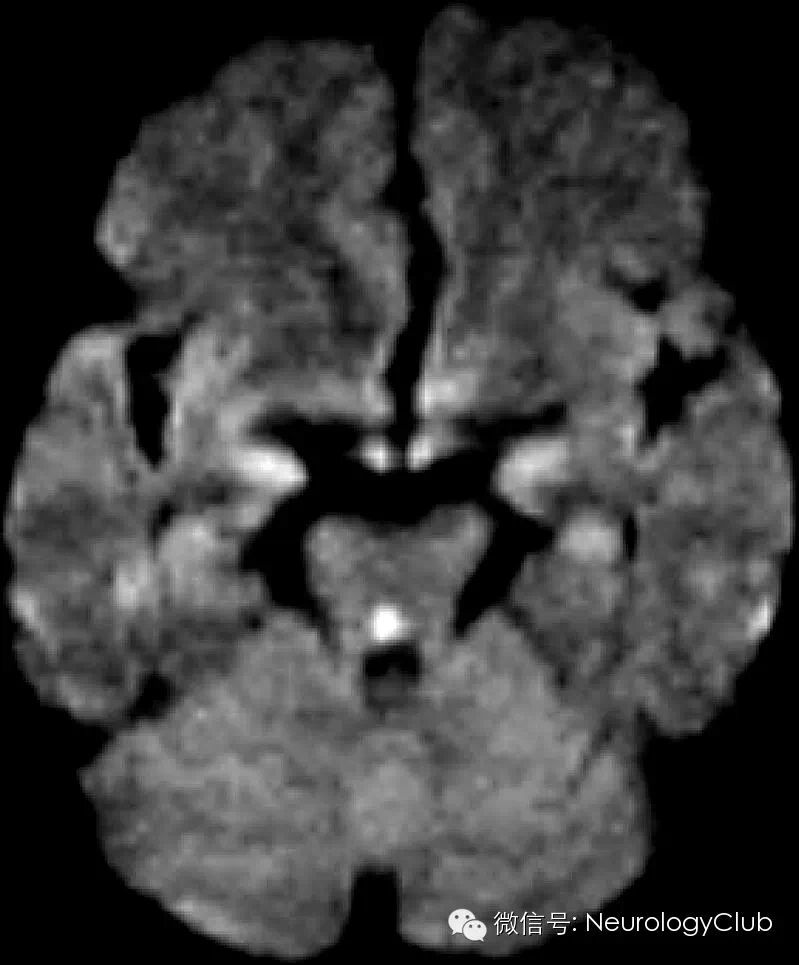

头颅影像学DWI序列见背侧中脑中部小的高信号病灶。